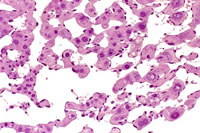

Dilated vascular spaces have replaced hepatic parenchyma in this hemangioma. High magnification shows dilated vascular spaces lined by flattened and sometimes dome-shaped endothelial cells and mild atrophy of the visible hepatic cords.